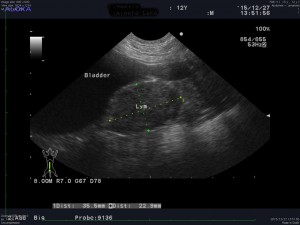

転移の有無や全身の健康状態を確認するために血液検査、胸腹部レントゲン検査、心臓及び腹部超音波検査を実施したところ、腰窩リンパ節の腫大が確認され、リンパ節転移あり、遠隔転移なしと診断しました。